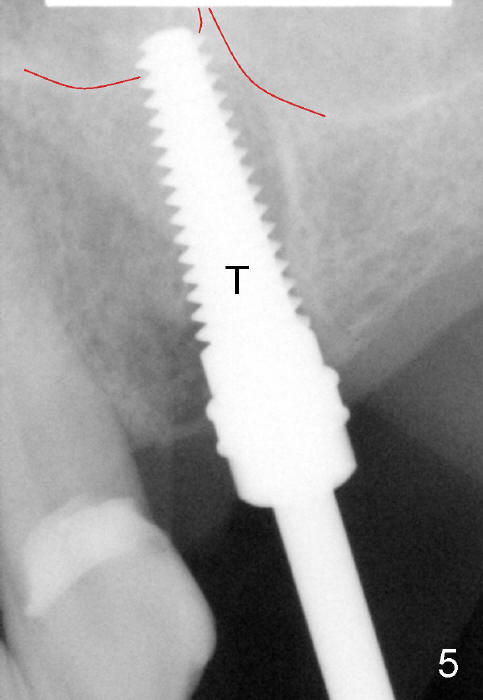

A 47-year-old lady has lost an upper left bridge (Fig.4,7). She is a dental phobic, but is concerned about cosmetics. Immediate implant and immediate provisional for the 1st bicuspid are easily accepted. There is a sinus septum above. Intraop PAs show that 4.5x17 mm tap (Fig.5) and 5x17 mm implant (Fig.6, insertion torque > 60 Ncm) are placed mesial to the septum without sinus membrane perforation. An abutment is placed immediately and an immediate provisional is fabricated.